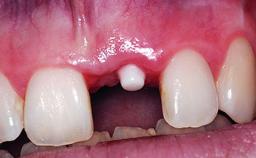

A 30-year-old patient presented at our clinic with a chief complaint of pain in her endodontically treated right maxillary central incisor (tooth 11) with a post-and-core and a fixed single crown. She had a very high lip line, a medium to thin soft-tissue phenotype, and a medium scalloped gingival contour. She also had high esthetic expectations because of her young age and beautiful smile. However, her expectations were realistic and she understood the risks of the treatment. At the initial clinical examination there was a slight mobility of tooth 11; no fistula was observed. The patient also had a single crown on the adjacent tooth 21. Both restorations were old and esthetically deficient. A digital periapical radiograph showed a very small periapical radiolucency, a thick intraradicular post, and no separation between root fragments.